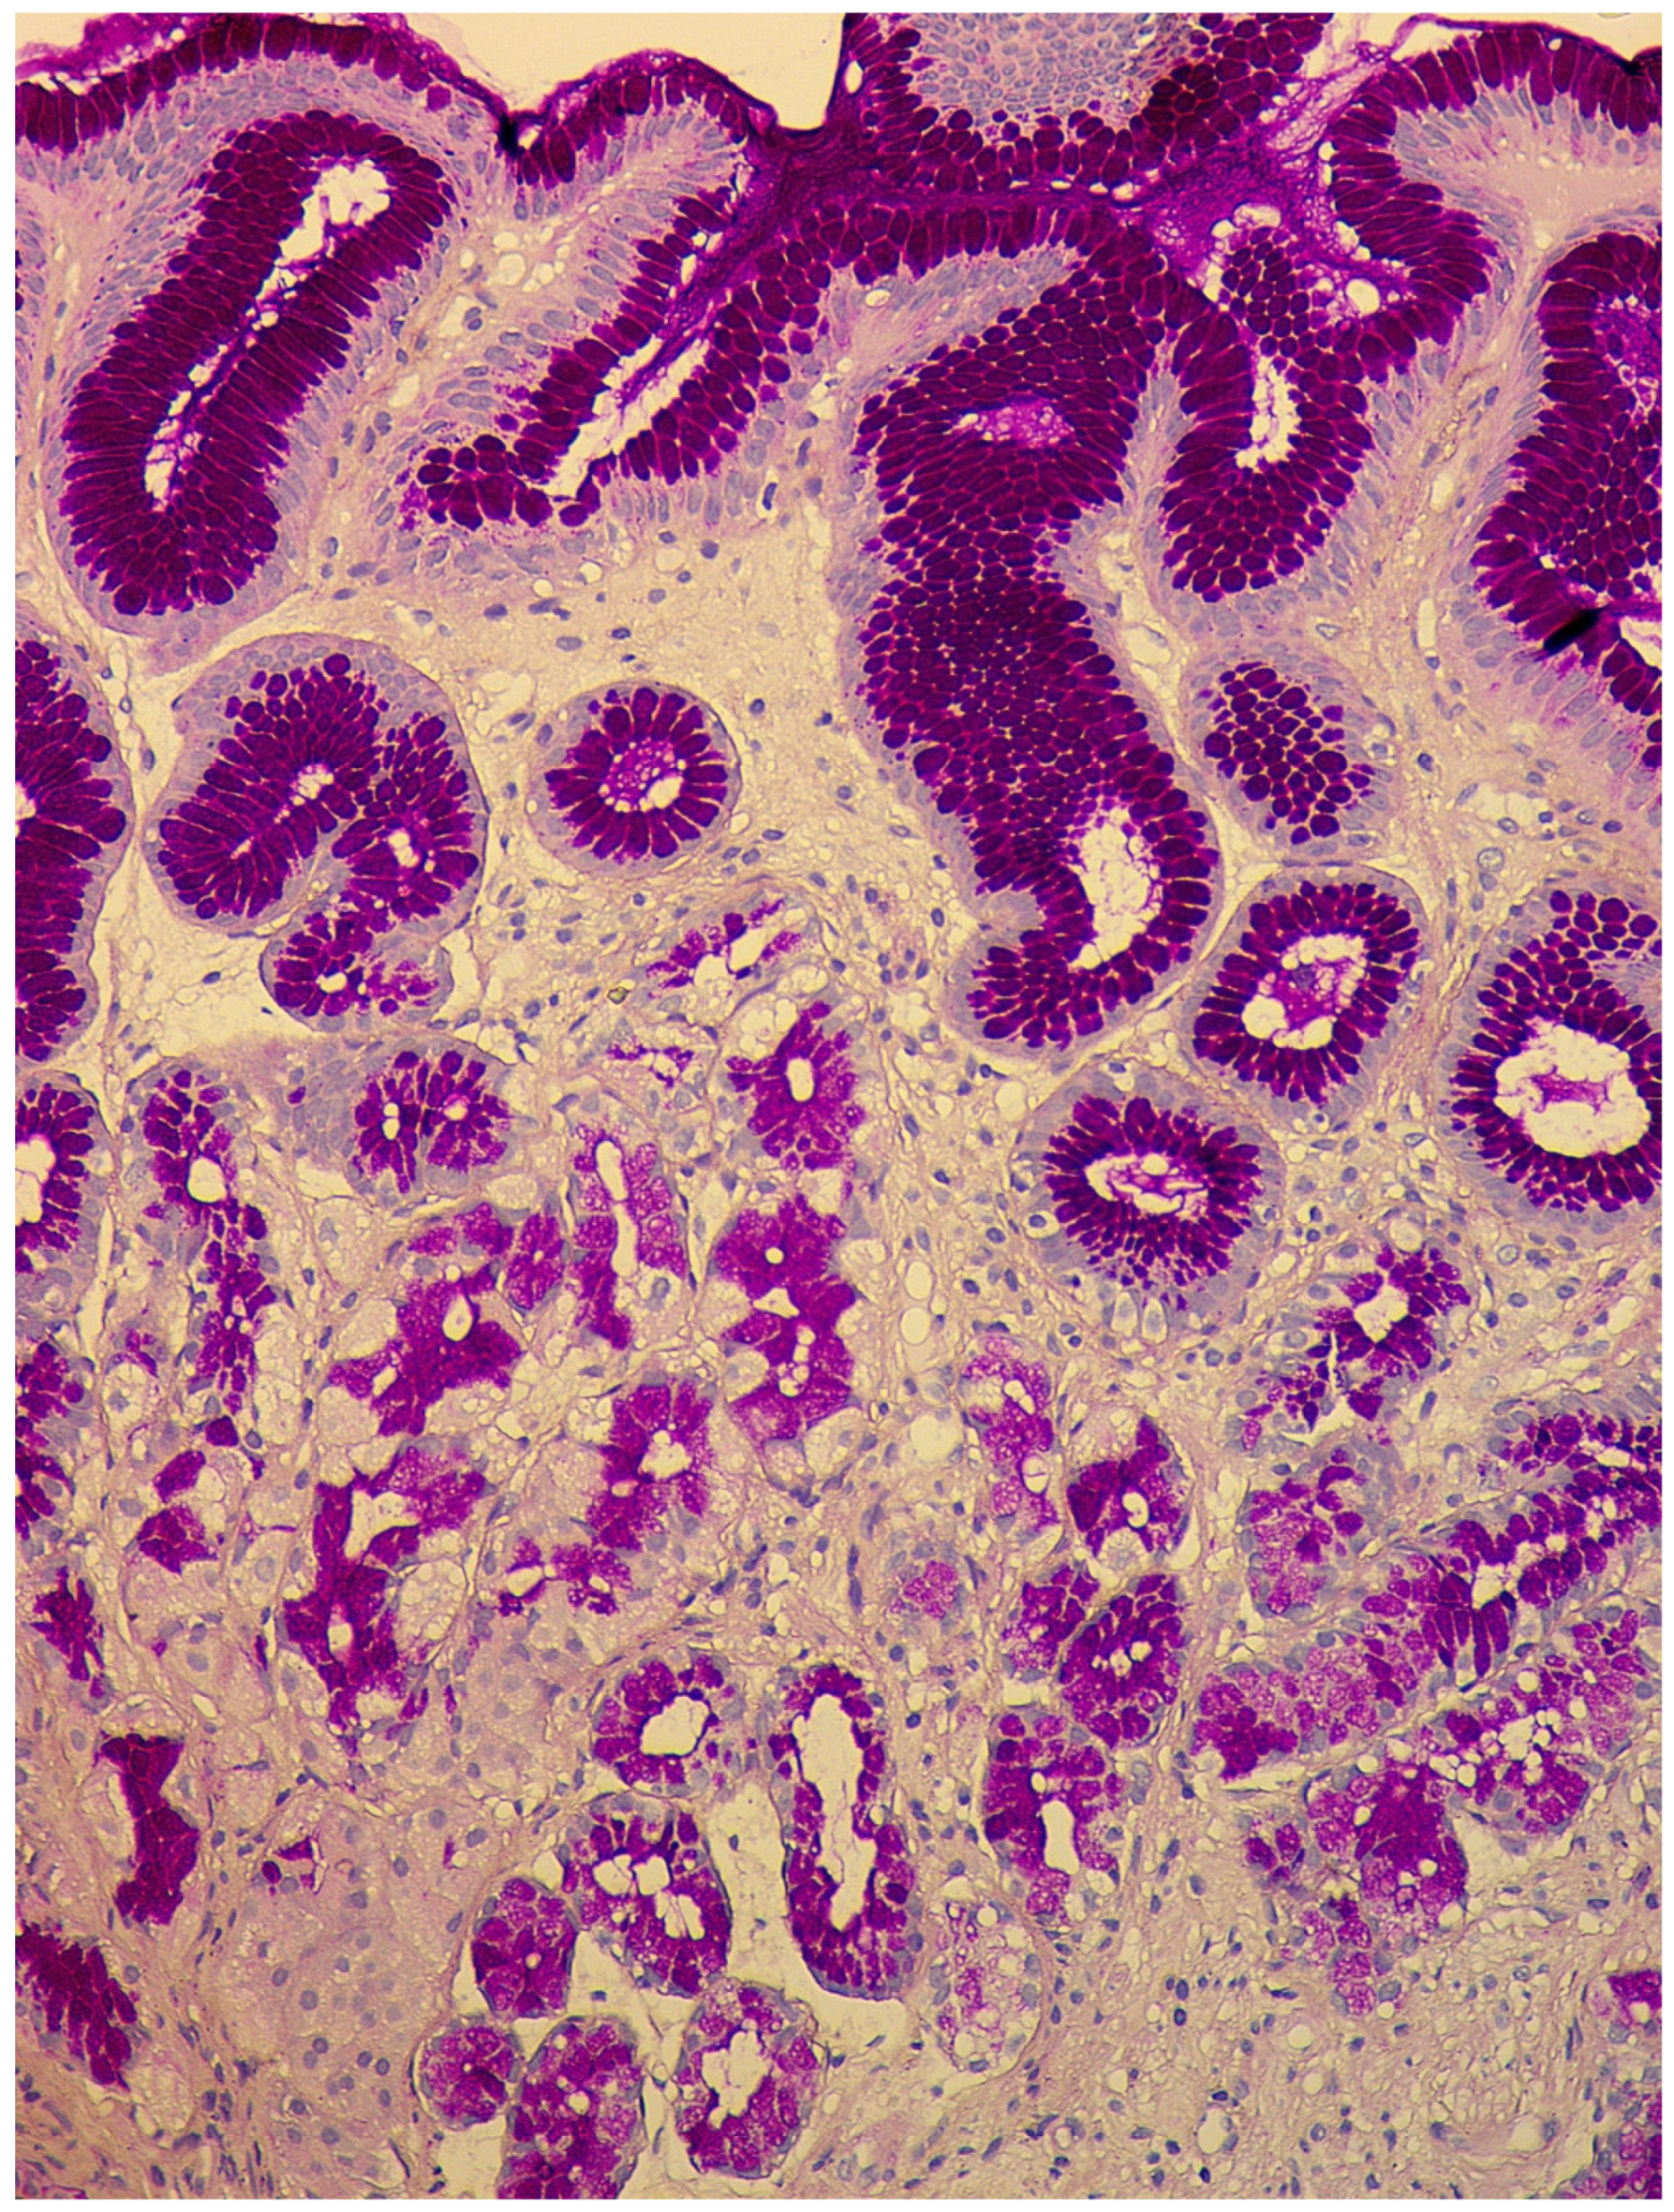

In the second stage, or expanded (florid) stage, pronounced atrophy of acid-producing glands develops; diffuse lymphoplasmacytic infiltration of the lamina propria is characteristic of a decrease in the height of the glands and an increase in the thickness of the foveolar component. The prevalence of intestinal metaplasia is higher than in the previous phase, but pseudopyloric metaplasia plays the main role in the remodeling of gastric mucosa (Figure 2). In recent years, this type of metaplasia, with the formation of glands resembling the antral glands, is associated with a separate phenomenon—a cell line with the expression of spasmolytic polypeptide (SPEM—spasmolytic polypeptide-expressing metaplasia). The appearance of this cellular rearrangement is associated with an increased risk of an intestinal-type gastric cancer developing in patients with CAG [44,45,46]. In this stage, due to the presence of pronounced atrophic changes with selective involvement of the stomach’s glands, the morphological picture becomes pathognomonic. However, establishing the presence of antibodies to parietal cells and intrinsic factors also remains necessary to confirm the diagnosis.

Figure 2.

Autoimmune gastritis. Biopsy from the gastric body. Severe pseudopyloric metaplasia with the appearance of mucus-producing cells in place of the fundic glands (cytoplasm magenta staining). Periodic acid-Schiff stain. ×200 (from the personal archive of Professor S.I. Mozgovoi).